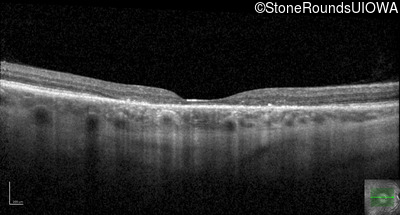

Optical Coherence Tomography - Right - 20/50 +2 sc

Exemplar / OCT Stack